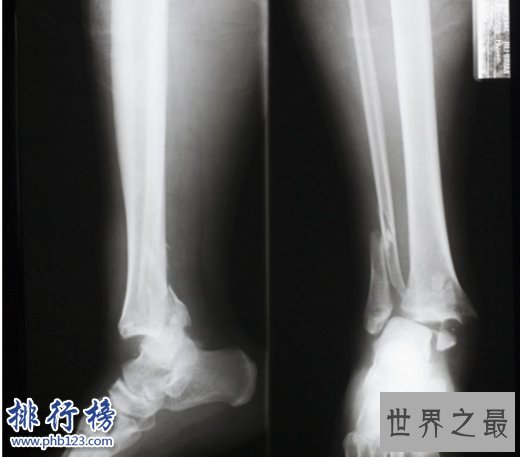

5. X光

发明时间:1895年

德国物理学家伦琴在实验室中工作时,突然发现另一边荧光纸板上出现了自己手掌骨骼,伦琴意识到,有一束神秘的光透过空气和血肉,投影到纸板上。伦琴想到可以利用这种光来透视人体,这对医学有很大的帮助。于是诞生了世界上第一幅X光片。